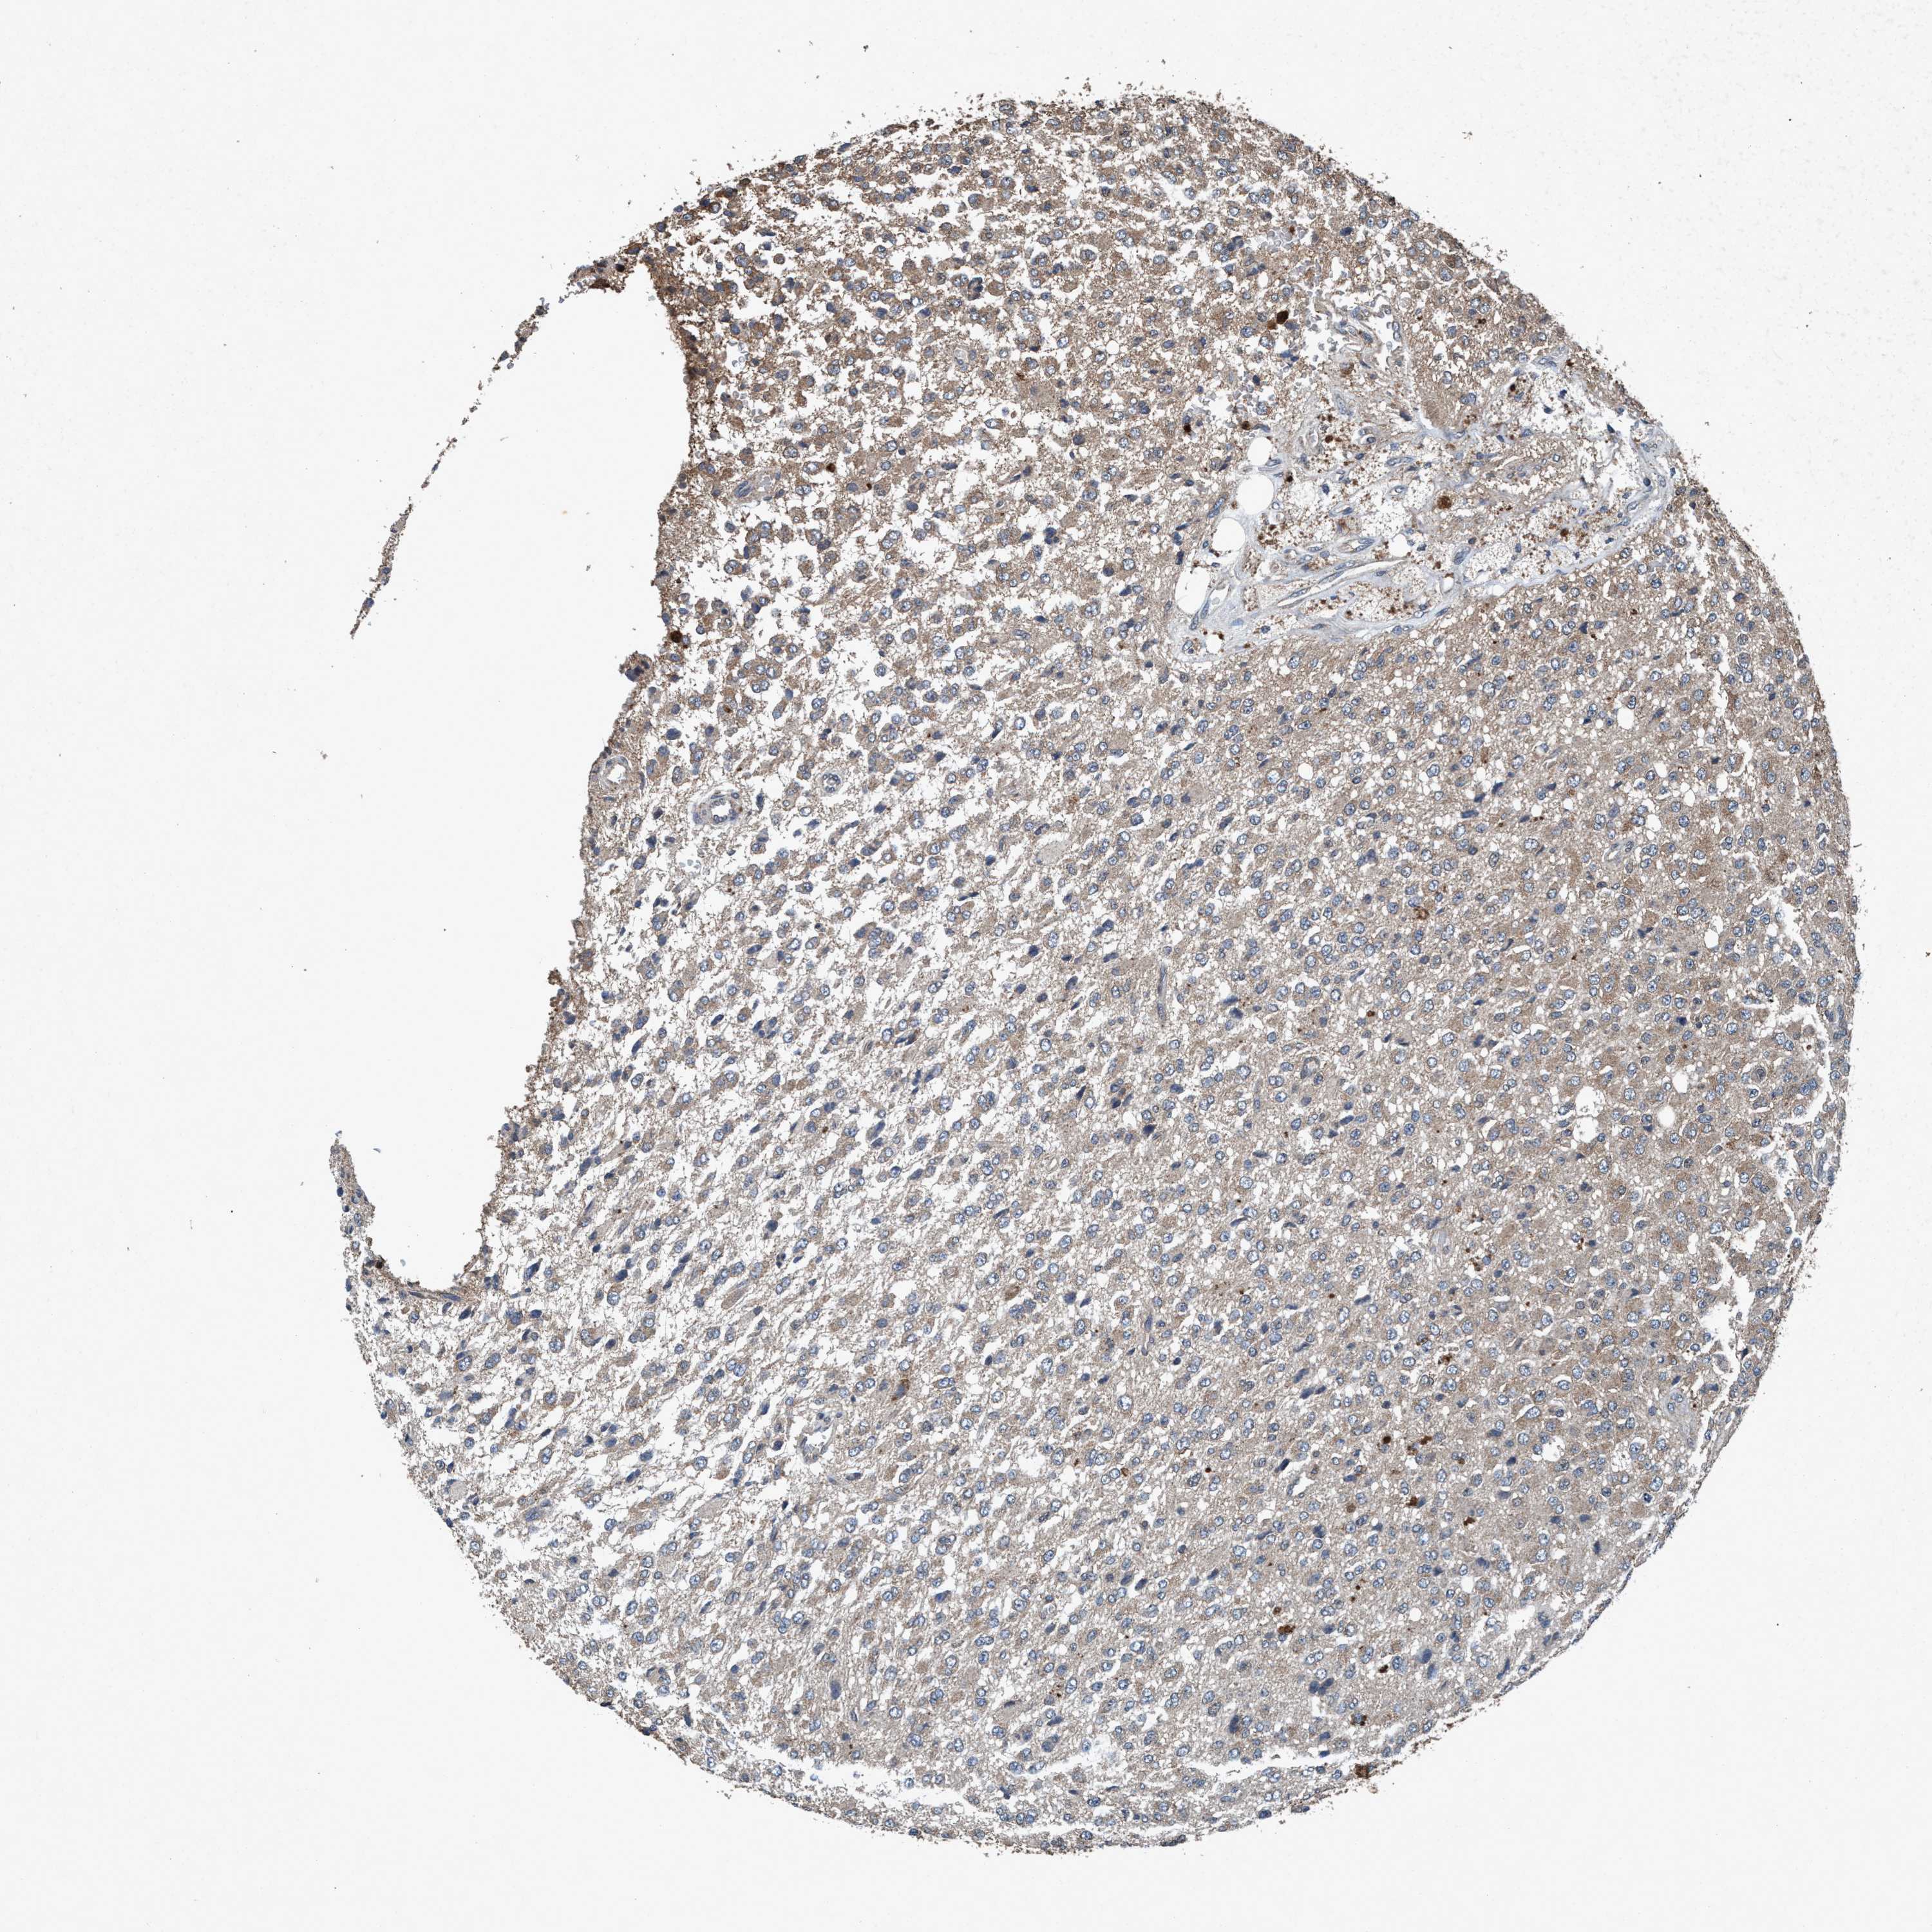

GLIOMA - Protein expressioni

A mouse-over function shows sample information and annotation data. Click on an image to view it in a full screen mode. Samples can be filtered based on level of antibody staining by selecting one or several of the following categories: high, medium, low and not detected. The assay and annotation is described here.

Note that samples used for immunohistochemistry by the Human Protein Atlas do not correspond to samples in the TCGA dataset.

Antibody stainingi

Antibody staining in the annotated cell types in the current human tissue is reported as not detected, low, medium, or high, based on conventional immunohistochemistry profiling in selected tissues. This score is based on the combination of the staining intensity and fraction of stained cells.

Each image is clickable and will lead to virtual microscopy that enables deeper exploration of all samples and also displays staining intensity scores, fraction scores and subcellular localization as well as patient and tissue information for each sample.

Antibody HPA064427

Antibody HPA075510

Antibody CAB021903

Staining

High

Medium

Low

Not detected

Intensity

Strong

Moderate

Weak

Negative

Quantity

>75%

75%-25%

<25%

None

Location

Nuclear

Cytoplasmic/membranous

Cytoplasmic/membranous,nuclear

Glioma, malignant, Low grade

Glioma, malignant, High grade